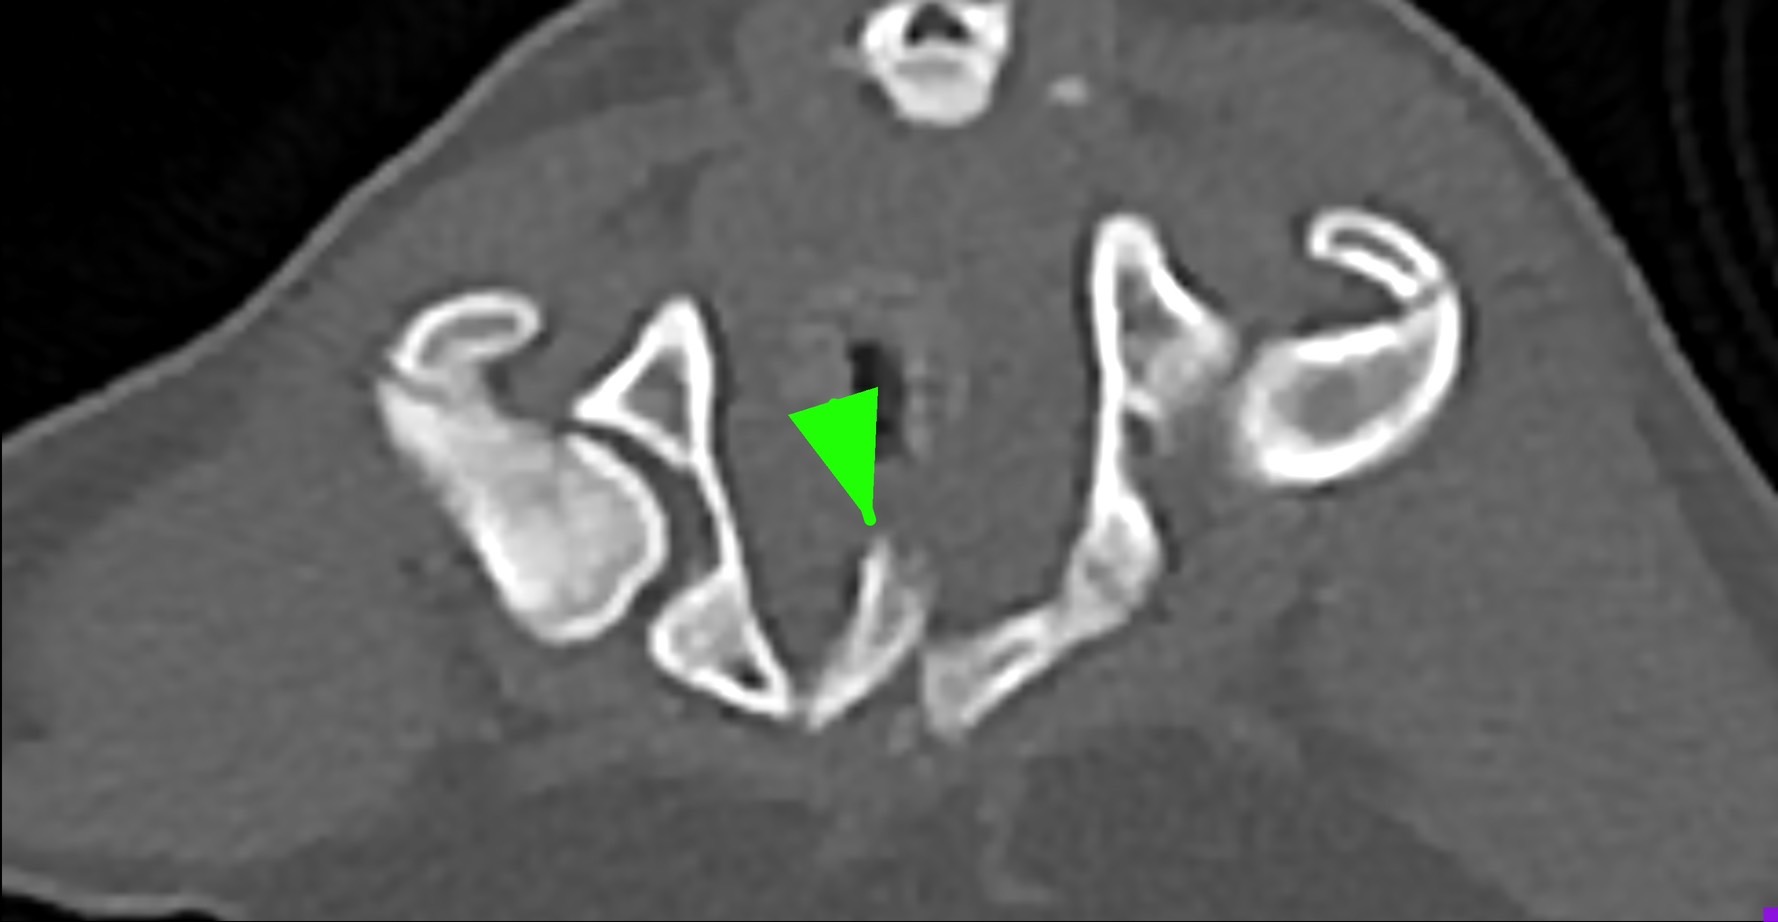

狗狗 車禍 骨盆骨折

狗狗的骨盆骨折相對於常見的四肢骨折 不容易單純靠xray 診斷及擬定手術計畫藉由電腦斷層影像的支援 能提高手術成功的機率

14kg 11歲的莓莓 術後10個月追蹤 行動自如一切正常喔

術前

術後

電腦斷層影像

骨盆骨折 評估手術計畫